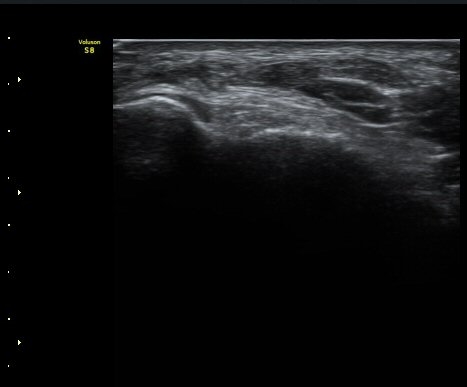

3ÁÖ ÈÄ ÃßÀû°Ë»ç»ó °üÀý³» ºÎÁ¾ÀÌ ¼Ò½ÇµÇ°í(±×¸² 6). Àü°Å°ñºñ°ñÀδëÀÇ Àú¿¡ÄÚ ºÎÁ¾Àº

°üÂûµÇ³ª ¿¬°á¼º ¼Ò½ÇÀº È®ÀεÇÁö ¾Ê´Â´Ù(±×¸² 8).